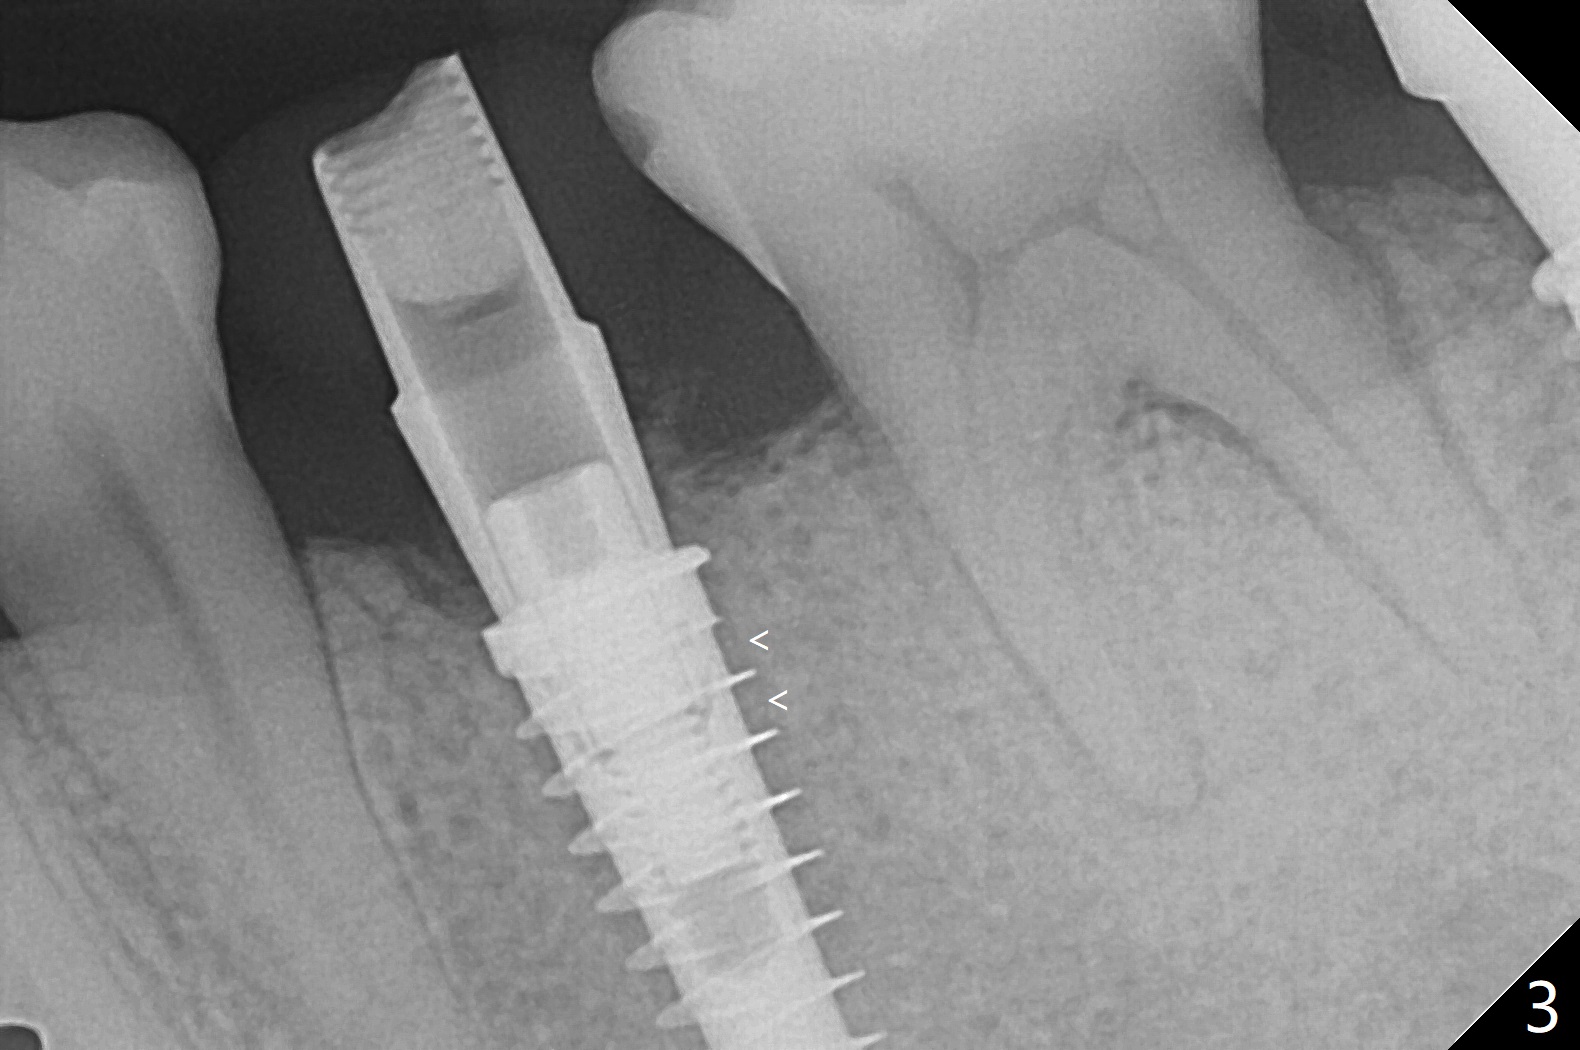

为了预防钻头遇到舌侧骨板而往颊侧偏移,有意不拔除第二前磨牙牙根。但是2.2毫米钻头钻洞很吃力,最后不得不拔除牙根,阻力骤然减少,顺利完成植入,而且颊侧间隙还够(图一,二),填入骨粉后远中螺纹间空间消失(图三箭头)。今后最后一个钻头完成钻洞后留在原位,周围放置适当量的骨粉,然后取出钻头,植入植体,这样空间可以比较全面充填。即刻种植没有颊侧偏移可能是因为设计时植体没有过多接触舌侧骨板(图四L)。第二磨牙延期种植需要切开是因为颊侧角化牙龈不足。术后两个月,前磨牙植体顶端似乎被牙槽嵴覆盖了(图五 *)。术后五个月,旋转7愈合基台,下面植体疼痛,可能与植体螺纹断裂有关(图六:>),5取模。